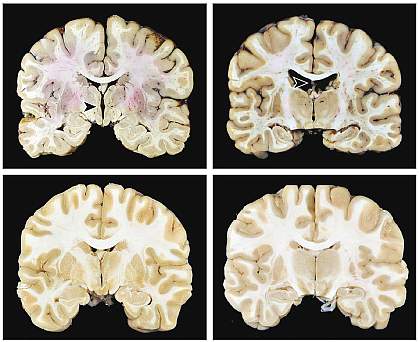

More than 40% of the donors (63 out of 152) had CTE based on established criteria. Nearly all cases of CTE were mild (stages 1 or 2 out of 4). Donors with CTE tended to be older than those without the disease. The most common cause of death among the donors was suicide, followed by unintentional drug overdose. The causes of death did not differ between those with and without CTE. Most of the donors with CTE were male, but one was female—a collegiate soccer player.

The team identified several abnormalities that occurred more often in the brains of people with CTE. These included structural differences as well as more macrophages (an immune cell) surrounding blood vessels in the white matter of the brain.